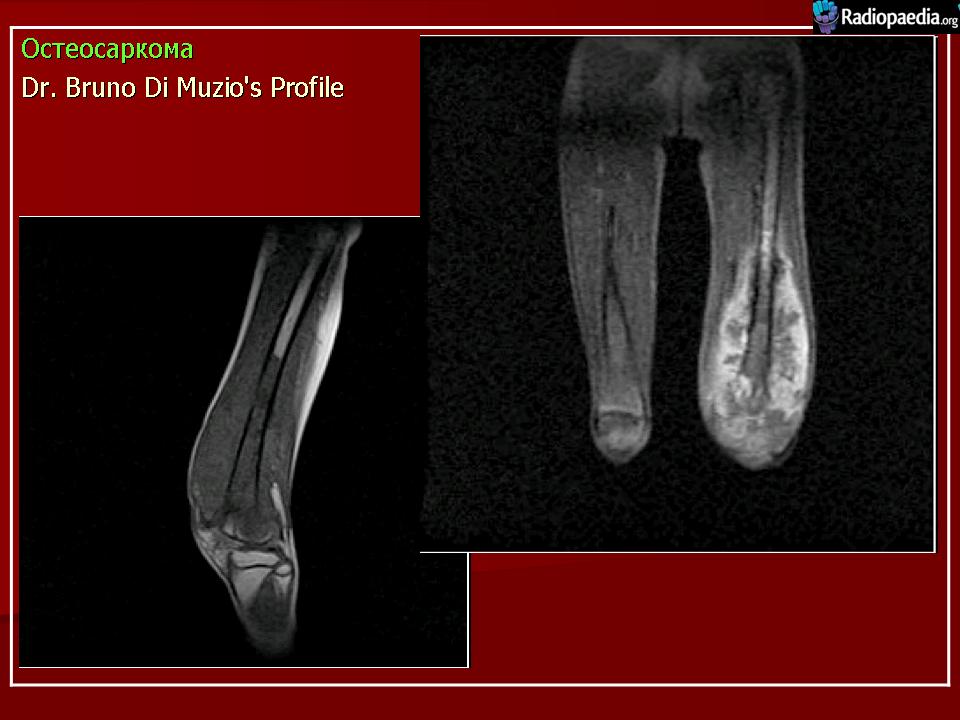

Остеосаркома

Остеосаркома (синонимы: центральная остеосаркома, остеофибросаркома, остеохондросаркома, медуллярная остеосаркома) - злокачественная опухоль, при которой новообразованная кость или остеоид продуцируются непосредственно самими опухолевыми клетками. Среди всех сарком кости, остеосаркома встречается наиболее часто и локализуется в длинных костях скелета.

Рентгенологическая картина. Типичной картиной является наличие очага смешанной деструкции кости с разрушением кортикальной пластинки и формированием мягкотканного компонента опухоли. В процессе роста опухоли, периост приподнимается или отслаивается от коркового слоя, это вызывает новое костеобразование, обычно проксимальнее основного узла, данное явление получило название козырька Кодмана. Зона поражения на рентгеновском снимке имеет различную плотность, а характер матрикса часто облаковидный. КТ и МРТ могут играть важную роль в определении распространенности опухолевого процесса. Радионуклидное сканирование скелета выявляет «skip» метастазы, многоузловые опухоли, системное поражение. В ряде клиник принято использовать артериографию, так как остеосаркомы - гиперваскуляризованные опухоли.